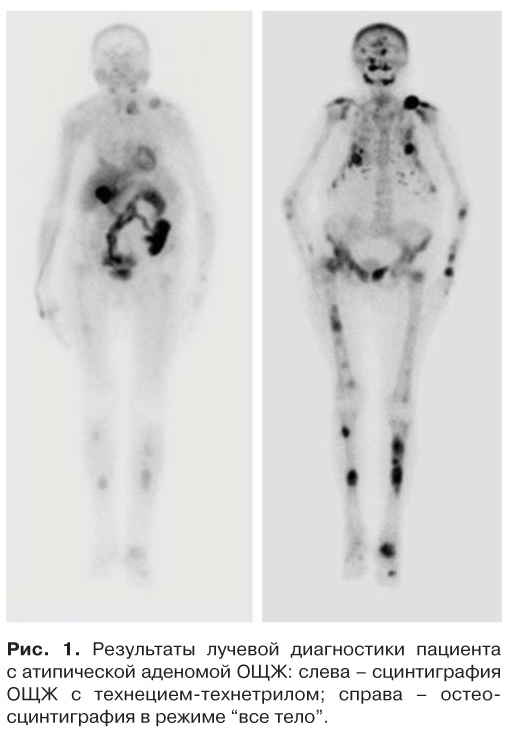

С целью топической диагностики выполнено: УЗИ ОЩЖ – визуализировано образование левой нижней ОЩЖ размерами 4,6 × 4,2 × 3,1 см пониженной эхогенности с жидкостными зонами, образование правой нижней ОЩЖ размерами 0,7 × 0,3 × 0,3 см; сцинтиграфия ОЩЖ c 99mТс-технетрилом (MIBI) в режиме ОФЭКТ/КТ, определялось образование с четкими контурами, размерами 4,3 × 3,4 × 4,0 см, активно накапливающее РФП позади средней и нижней трети левой доли щитовидной железы, распространяясь книзу от нижнего полюса. Позади нижней трети правой доли – образование размерами 0,8 × 0,4 × 0,6 см, с низкоинтенсивным накоплением РФП (рис. 1, 2). Результаты сканирования с MIBI подтвердили наличие одного образования ОЩЖ с характерным поражением костей.

Рис. 1. Результаты лучевой диагностики пациента с атипической аденомой ОЩЖ: слева – сцинтиграфия ОЩЖ с технецием-технетрилом; справа – остеосцинтиграфия в режиме “все тело”.

Для оценки распространенности патологических изменений в костях скелета проведена остеосцинтиграфия с 99mTc-технефором, по данным которой определялись множественные очаги гиперфиксации РФП в проекции костей черепа, плечевых суставов, дистального конца левой ключицы с переходом на акромиальную часть лопатки, всех ребер, костях предплечья с обеих сторон, шейном, нижне-грудном и поясничном отделах позвоночника, бедренных, большеберцовых костях, левом голеностопном суставе, костях таза. Также определялись множественные очаговые изменения структуры костной ткани (деформация контуров, истончение кортикальных пластин) в костях свода черепа, в обеих ключицах, лопатках, правой плечевой кости, ребрах. Наиболее выражены структурные изменения костной ткани в дистальной части левой ключицы с переходом на акромион лопатки (отмечается “вздутие” кости с крупноячеистой внутренней структурой и мягкотканным компонентом). Очаги в костях частично накапливали РФП. Принимая во внимание результаты КТ (множественные “бурые” опухоли в костях), накопление РФП в костях расценено как проявление фиброзно-кистозного остеита. Наличие выраженных метаболических изменений костной ткани также нашло свое отражение в повышении маркеров костной резорбции (С-концевой телопептид коллагена 1 типа 2,76 нг/мл (норма 0,01–0,69 нг/мл), остеокальцин 300 нг/мл (норма 11–41 нг/мл), щелочная фосфатаза 461 Ед/л (норма 50–150 Ед/л)).